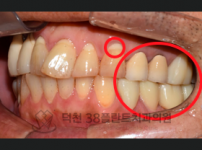

치료전후